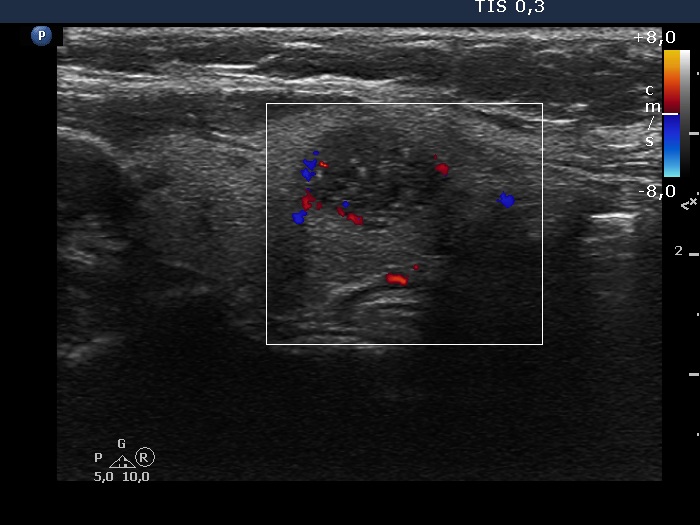

The shape of the nodule - case 2052 (ultrasonographic picture 3)

Left lobe, longitudinal scan. The vascularization is not specific.